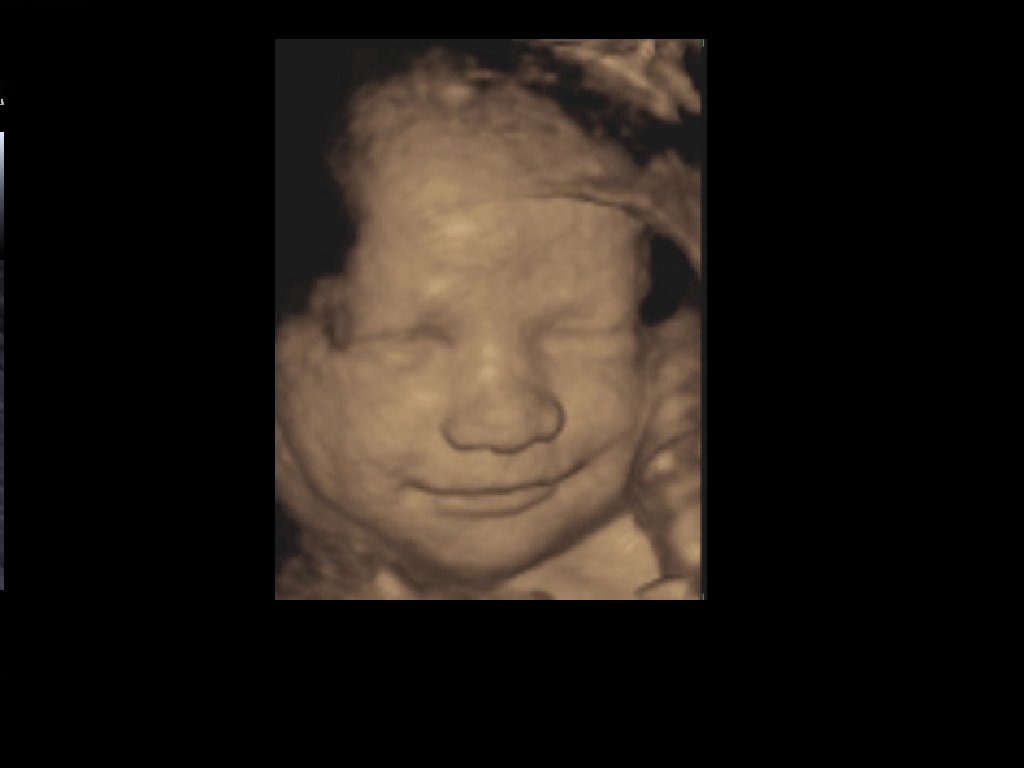

Vous avez la possibilité dans notre cabinet de bénéficier d'une échographie en 3D et 4D, pour une rencontre particulière avec votre bébé!

L’échographe, qui n’est rien d'autre qu’un ordinateur, reconstitue alors une image en 3 dimensions. Il ne s’agit donc pas d’une photographie et l’aspect peut parfois être imparfait.

L’échographie en 4D est une échographie en 3D, mais en mouvements.

L’échographie en 3D n’est pas toujours réalisable. Sa faisabilité dépend de la position du bébé et de la quantité de liquide amniotique. Elle ne présente pas d’intérêt médical particulier en l’absence d’anomalie, si ce n’est le plaisir de visualiser le visage de votre bébé !